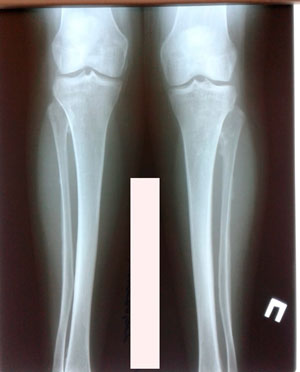

Рентген перед фиксацией

IMG_4885-09-08-19-12-41.JPG

IMG_4884-09-08-19-12-41.JPG